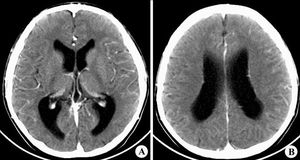

首先要抗水腫治療,可靜脈點滴甘露醇和利尿劑利尿,同時限制液體的輸入量,以免加重水腫,一般昏迷病人不能進(jìn)食者,每天需要的生理需求量為2000-2500ml左右,若是發(fā)燒及有傷口滲出則要加上損耗量.您說的病人的意志力越來越弱是怎么回事呢,是說他的生命體征包括心率血壓脈搏和體溫四項不正常了是嗎?腦損傷過了腦水腫這一危險期后病情可能會好轉(zhuǎn)一些,也有希望蘇醒,所以您們不用太擔(dān)心,配合好醫(yī)生的治療,然后注意以下的護(hù)理工作讓病人脫落危險期就好了:昏迷容易引起合并癥使病情加重,甚至成為病人死亡的原因.1,預(yù)防吸入性肺炎吸入性肺炎是一種嚴(yán)重的并發(fā)癥,常表現(xiàn)為發(fā)熱,呼吸困難,紫紺等.護(hù)理時注意:(1)昏迷病人尤其有顱內(nèi)壓增高,嘔吐者,頭要偏向一側(cè),以便口腔內(nèi)的分泌物順口角向外引流,可防止分泌物吸入呼吸道造成吸入性肺炎.(2)做好口腔護(hù)理,保持口腔清潔,減少口腔常居菌的的密度.(3)病情穩(wěn)定后,可下胃管鼻飼,既可提供充分營養(yǎng),又可避免嗆咳和吸入異物.(4)對已發(fā)生感染者除以上措施外,按醫(yī)囑給予抗生素治療.(5)及時吸出口腔和氣管內(nèi)分泌物,或嘔吐的胃內(nèi)容物,必要時做氣管切開.2,預(yù)防肺部感染和墜積性肺炎(1)保持呼吸道通暢,分泌物多時要及時吸痰,吸痰用物要嚴(yán)格消毒,特別是為氣管切開病人護(hù)理時,要嚴(yán)格無菌操作.并每2-3小時翻身拍背1次,協(xié)助排痰.(2)保持鼻,口腔清潔,及時清除鼻腔分泌物和結(jié)痂,認(rèn)真做好口腔護(hù)理.(3)若肺部已有感染或肺不張,可給予霧化吸入及全身應(yīng)用抗生素.3,預(yù)防褥瘡患者意識喪失,處于被動體位,長期皮膚受壓,循環(huán)欠佳,加之汗尿等排泄物對皮膚刺激等,導(dǎo)致局部皮膚抵抗力降低,以及床單不平或床鋪不清潔而使之發(fā)生褥瘡.所以,必須注意皮膚護(hù)理,做到勤翻身,勤檢查,勤擦洗,勤按摩,勤整理,勤交待.4,預(yù)防泌尿系感染昏迷常伴有尿潴留和大小便失禁,尿潴留本身易伴發(fā)泌尿系感染,經(jīng)常導(dǎo)尿更容易引起感染.護(hù)理時應(yīng)注意:(1)要注意病人的膀胱充盈度,盡早導(dǎo)尿,尿失禁者要及時更換尿布,擦洗干凈會陰,防止尿液中化學(xué)成分及潮濕對皮膚的刺激.(2)導(dǎo)尿和留置導(dǎo)尿應(yīng)嚴(yán)格無菌操作,定時膀胱沖洗.(3)對已發(fā)生感染者除加強(qiáng)沖洗外,全身給予高效,足量的抗生素,多補(bǔ)充水分,促進(jìn)排泄,有利于控制感染.(4)加強(qiáng)膀胱肌功能鍛煉定時開放尿管,夾緊尿管,每1-3小時放尿一次,并逐漸延長時間,在膀胱空虛時按摩.。